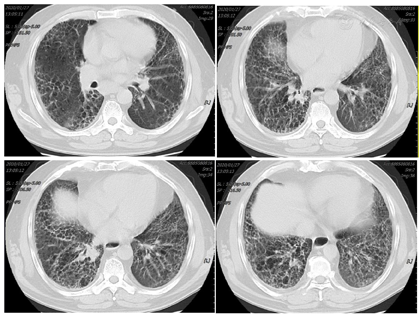

患者经治疗后肿瘤病灶明显缩小(图3,图4,图5,图6,图7,图8),定期于我院随访复查,目前一般情况良好,未见复发及远处转移。

PD-L1是一种跨膜糖蛋白,属于B7家族成员之一,一级结构包括290个氨基酸,亦由胞外区、疏水跨膜及尾部胞浆区组成[2]。有研究发现,PD-L1蛋白广泛表达于活化T淋巴细胞、巨噬细胞、B细胞等免疫细胞,还表达于多种类型的恶性肿瘤细胞表面,比如乳腺癌、胶质瘤、恶性黑色素瘤等[3]。PD-L1与其受体程序性死亡分子1 (PD-1)结合形成PD-1/PD-L1通路,该通路可介导形成机体的免疫抑制微环境,参与肿瘤细胞的免疫逃逸,继而促进肿瘤的发展。研究发现,27%~50%的肺癌患者可表达PD-L1[4,5],Koh等人[6]发现,在肺腺癌组织中PD-L1的阳性表达率为59%,且其阳性表达与患者淋巴结转移、组织分化程度及吸烟有关。有研究结果表明,肺鳞癌组织PD-L1阳性表达明显高于正常肺组织,PD-L1阳性表达与患者pTNM分期、淋巴转移有关,提示PD-L1在肺鳞癌的发生、进展过程中具有重要作用[3]。但目前单独研究PD-L1对肺鳞癌患者预后影响的报道甚少,尤其是伴有肺间质纤维化的肺鳞癌患者的相关研究更少,有待于大规模的临床试验。PD-L1抑制剂虽然可以达到预期的抗肿瘤效果,但这是一个非常复杂的过程,也有发生免疫相关不良事件的风险,包括诱发各种器官的炎症反应[7,8]。目前,其背后的机制仍不清楚,但先前的肺部疾病可能是免疫检查点抑制剂诱发肺炎的一个危险因素[9],所以由于肺炎的风险增加,肺间质纤维化合并肺癌患者接受免疫检查点抑制剂治疗的报道甚少。在以往的研究中,与传统非小细胞肺癌的化疗方案相比,抗PD-1治疗导致重度免疫相关性肺炎的发生率较高,但抗PD-L1治疗则不然[10]。也有研究显示,使用PD-1抑制剂患者3/4级免疫相关性肺炎的发生率仅略高于使用PD-L1抑制剂的患者[11]。此例病人为肺鳞状细胞癌伴肺间质纤维化,肿瘤细胞的PD-L1阳性表达百分比高达78%,因此在GP方案化疗的同时联合应用PD-L1抑制剂度伐利尤单抗,并在化疗与免疫联合治疗5疗程后以度伐利尤单抗单药维持。复查时可见右肺下叶的肿瘤病灶迅速且明显缩小,肺间质纤维化未见进展。患者治疗初期躯干部有散在皮疹出现,经抗过敏治疗后皮疹消失。患者1年半来复查病情稳定,未见复发及除淋巴结以外的其他部位转移,没有报告过除散在皮疹以外的免疫相关不良事件发生,也进一步证实了肺鳞癌病人化疗联合抗PD-L1药物作为一线治疗方案的可行性和安全性,为临床工作中肺鳞癌病人的治疗提供了新的思路。但目前病例数少,有待于大规模的临床试验。我们期望,在不远的未来,免疫治疗可使越来越多的肺癌患者获益。